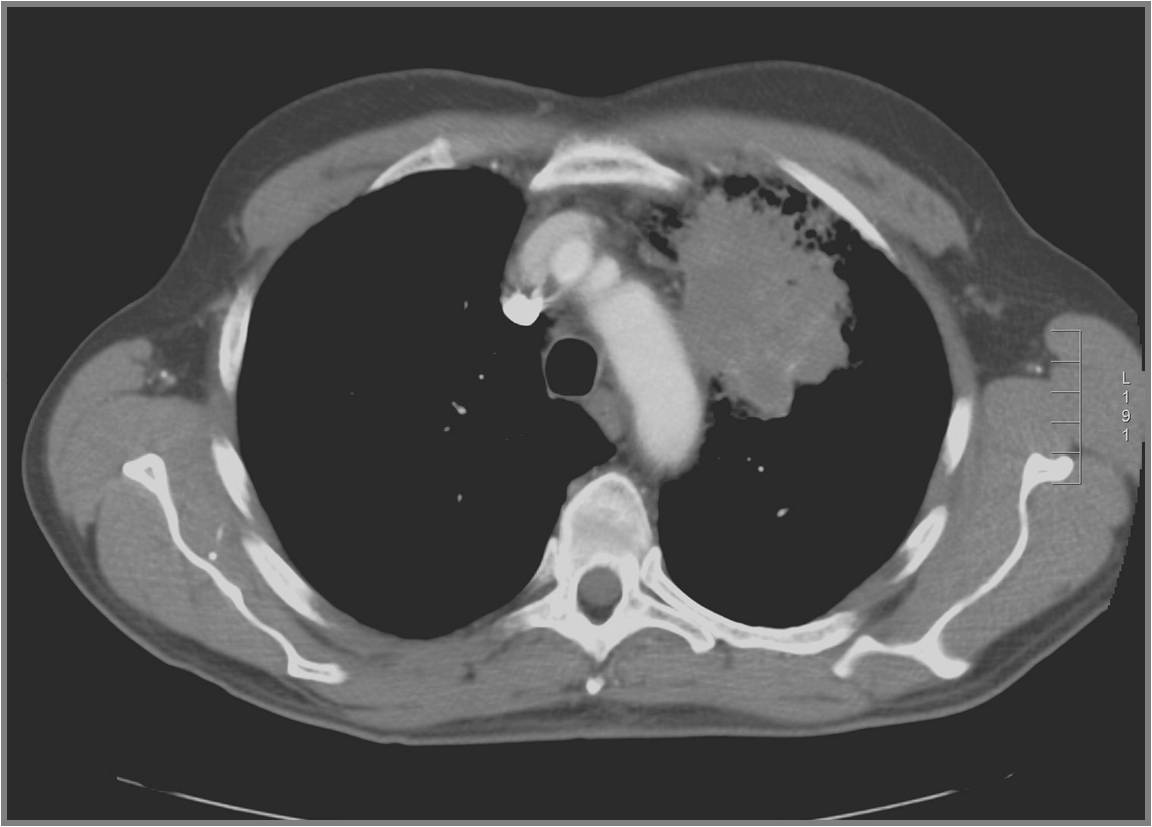

CT scan ngực

Hình ảnh của toàn bộ lồng ngực sẽ được cắt

ngang, cắt dọc thành từng lát cách nhau vài milimet do đó những khối u, khối

hạch có kích thước vài milimet cũng sẽ được phát hiện. CT ngực cũng cắt lát qua

gan để phát hiện có di căn gan hay không.